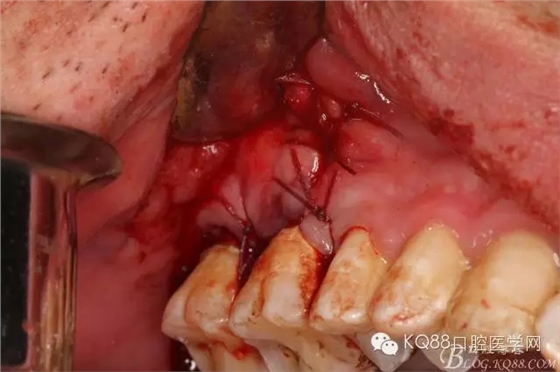

圖9.清理缺損骨腔內(nèi)的膿性分泌物及炎性肉芽組織,目的是找到18在哪里,隱約可以看到18白色的小樣子喲。

圖10.去除了覆蓋在18牙冠表面的肉芽組織,暴露出18的部分牙冠。

圖11.千辛萬苦,總算看到18的合面了,唯一難做的就是牙齒在里面打轉(zhuǎn)轉(zhuǎn),固定不住牙,也無法夾持住它,好郁悶。

圖12.沒辦法,只能往16旁邊去了點(diǎn)骨質(zhì)。才把18它呼喚出來。病人說他的嘴巴快被拉扯了。

圖13.取出18后,出現(xiàn)的巨大空腔,上頜竇粘膜完全破損。

圖14.大量的生理鹽水沖洗竇腔,使炎性分泌物完全沖洗干凈。

圖15.缺損處填塞膠原蛋白海綿。

圖16.可吸收性縫線縫合